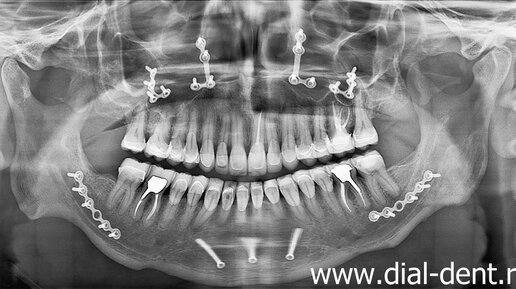

В нашу клинику пришел молодой мужчина с пожеланием поменять пару пломб, которые постоянно выпадали. Но в процессе диагностики, стало ясно, что пломбы выпадают не просто так. Корень проблемы – неправильный...

Молодой мужчина обратился в Семейный стоматологический центр "Диал-Дент" для замены старых коронок. Коронка на верхнем переднем зубе из металлокерамики установлена давно, она не очень подходит к другим цветам по цвету и форме, а недавно стал сильно заметен металлический край у коронки. Так как это передние зубы, мужчина хотел заменить коронку на более эстетичную. Также есть две металлические коронки на жевательных зубах (по одному сверху и снизу), которые заметны при разговоре или широкой улыбке...